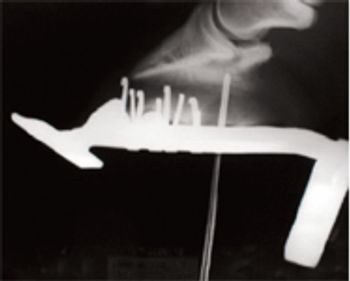

One practitioner's 13-step protocol to help horses suffering from this painful condition.